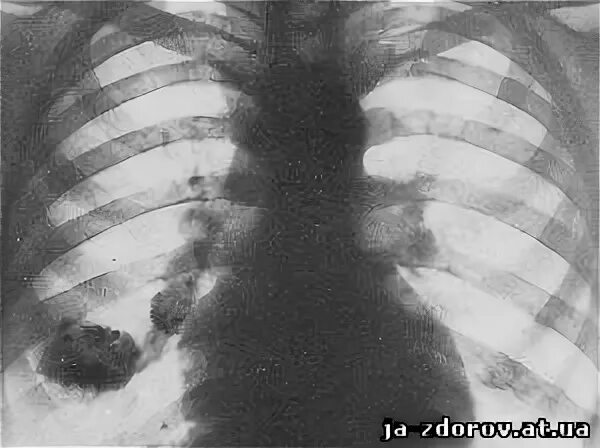

Очаг симон